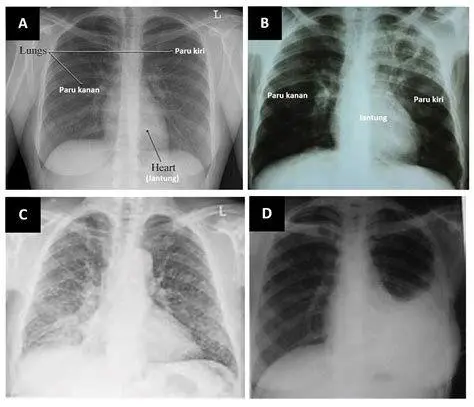

Jika Anda merasakan adanya ciri ciri tbc pada diri sendiri atau kerabat, jangan menunda untuk melakukan pemeriksaan medis. Dokter biasanya akan melakukan serangkaian tes seperti Tes Cepat Molekuler (TCM), rontgen dada, dan tes darah. Pengobatan TBC bukanlah hal yang instan. Pasien diwajibkan mengonsumsi kombinasi antibiotik selama minimal 6 hingga 9 bulan tanpa terputus.